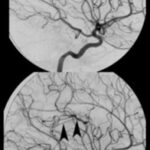

En primer lugar, se puede tratar el caso de los adictos al cannabis, cuya droga tiene efectos sobre el sistema endocannabinoide y en las áreas cerebrales vinculadas con la regulación de las emociones y el estrés. Un estudio de casos y control demostró mediante tomografía por emisión de positrones (PET) cómo la exposición crónica al cannabis, específicamente al THC, reduce la respuesta cerebral a la dopamina, y por ende, mayor puntuación de emocionalidad negativa en los adictos a esta sustancia respecto de los que no lo son. Esto se demostró con el uso de fármacos estimulantes, como el metilfenidato. Este mismo fenómeno también se ha observado con drogas como el alcohol, la cocaína y la nicotina. El cannabis también ocasiona una disminución en el metabolismo de la glucosa cerebral en el cuerpo estriado, tálamo y mesencéfalo(15) (ver Imagen 3).

Otro caso que conviene referir es el de una mujer de 19 años, quien acudió al servicio de guardia por dolor de cabeza agudo. Se le realizó una TC que mostró una hemorragia intraventricular con un posible componente parenquimatoso cerca de la pared del ventrículo derecho, a partir del abuso de cocaína en combinación con alcohol (ver Imagen 8). De igual modo, la angiografía evidenció una malformación arteriovenosa coroidea alimentada por la arteria coroidea lateral posterior(17) (ver Imagen 9).